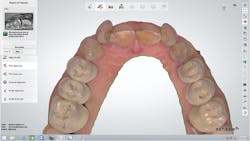

A 67-year-old female executive presented after becoming very self-conscious about the appearance of her anterior teeth (figure 1). During the consultation appointment, a thorough examination was performed, and scanned intraoral 3-D images and impressions (Trios, 3Shape) were obtained. Both arches and the bite registration were scanned (figure 2).

The scans were immediately evaluated chairside with the patient. When the maxillary scan was viewed from the occlusal aspect (figure 3), the extent of the rotation of her two lateral incisors became dramatically apparent to the patient. It was also pointed out and explained to her that both central incisors were positioned lingually due to the severe crowding of her arch.

Figure 2: Intraoral 3-D images and impressions of both arches and the bite registration were obtained and used to help plan and explain the treatment to the patient.

Figure 3: The extent of the rotation of the lateral incisors became dramatically apparent when viewing the maxillary scan from the occlusal aspect.